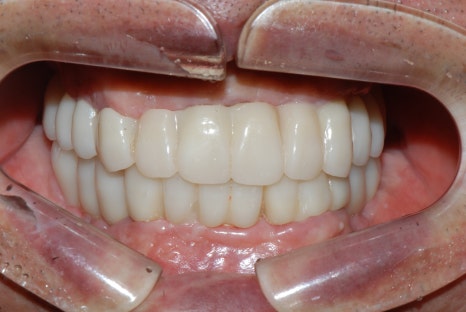

전체 임플란트 상부 보철을 세팅한 뒤 사진입니다.

총 6개월의 치료 기간이 소요되었습니다.

[동일 인물이며 동일 환경에서 촬영됨 / 치료 기간 : 24.02.15 - 24.09.10]

상실된 치아로 인해 입술이나 볼이 꺼져 보였던 모습이 개선되고,

하안모 길이와 얼굴 윤곽이 정상에 가깝게 복원된 것을 확인하실 수 있습니다.^^

게다가 치료 후 상실되었던 치아들이 다시 제 위치로 자리를 잡게 되면서

반대교합도 정상 교합으로 회복되었습니다.

▲ 상악 치아가 하악 치아를 덮는 정상교합 형태 / 서울전체임플란트잘하는치과